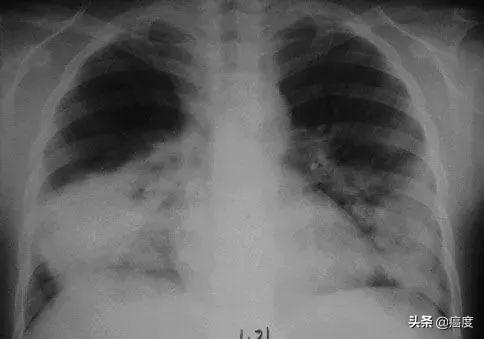

摘要:全球关注的肺炎事件最新进展表明,虽然取得了一定成果,但仍面临诸多挑战。目前,全球正密切关注疫情动态,共同应对病毒传播带来的威胁。随着病毒变异和防控措施的推进,新的挑战不断出现,如病毒传播变异速度加快、疫苗接种不均等问题。全球需加强合作,共同应对肺炎事件带来的挑战,保护人类健康。

自肺炎事件爆发以来,全球各国都在积极应对,从疫苗研发到治疗手段的进步,人类一直在与病毒赛跑,最新数据显示,全球范围内已经取得了显著进展,许多国家在疫苗研发方面取得了突破性成果,大规模接种工作正在有序进行,科技的进步也促使新型治疗手段的涌现,为患者带来了更多的希望。

尽管全球范围内已经取得了显著进展,但肺炎事件仍然面临着诸多挑战,病毒变异的速度超出预期,给疫苗研发和防控工作带来了极大的困难,全球疫苗接种率的不平衡也是一个亟待解决的问题,一些国家的疫苗接种工作取得显著成效,但仍有许多国家的接种率较低,可能导致疫情在全球范围内的反复,医疗资源的不均衡也是一大挑战,一些地区面临着医疗资源短缺的问题,使得患者的治疗更加困难。